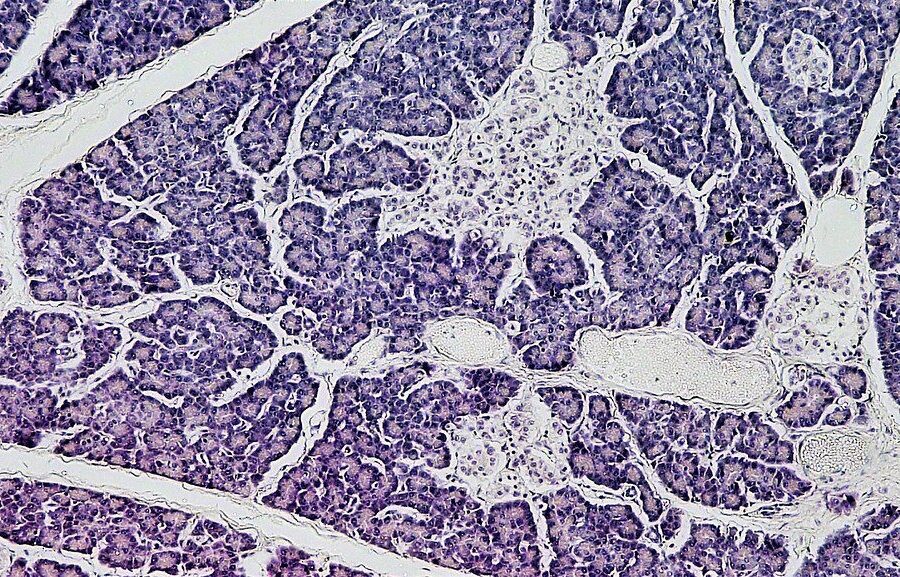

Kasa – vienas svarbiausių virškinimo sistemos organų, sveriantis vos 70–80 gramų. Ji gamina virškinimo fermentus ir hormonus, reguliuojančius gliukozės kiekį kraujyje. Nepaisant nedidelio dydžio, jos funkcijos yra gyvybiškai svarbios visam organizmui.

Eksokrininė kasos funkcija – virškinimo sulčių gamyba. Jose esantys fermentai skaido baltymus, riebalus ir angliavandenius, kad šios maistinės medžiagos galėtų būti pasisavinamos žarnyne. Sutrikus šiam procesui, atsiranda maisto nepakankamo suvirškinimo ir įsisavinimo problemų, kurios ilgainiui silpnina organizmą.

Endokrininė funkcija susijusi su hormonų – insulino, gliukagono ir somatostatino – gamyba. Insulinas mažina gliukozės kiekį kraujyje, gliukagonas ją didina, o somatostatinas padeda palaikyti šių hormonų pusiausvyrą. Šių procesų veiksmingumas priklauso nuo daugelio veiksnių, įskaitant mitybą ir bendrą virškinimo sistemos būklę.